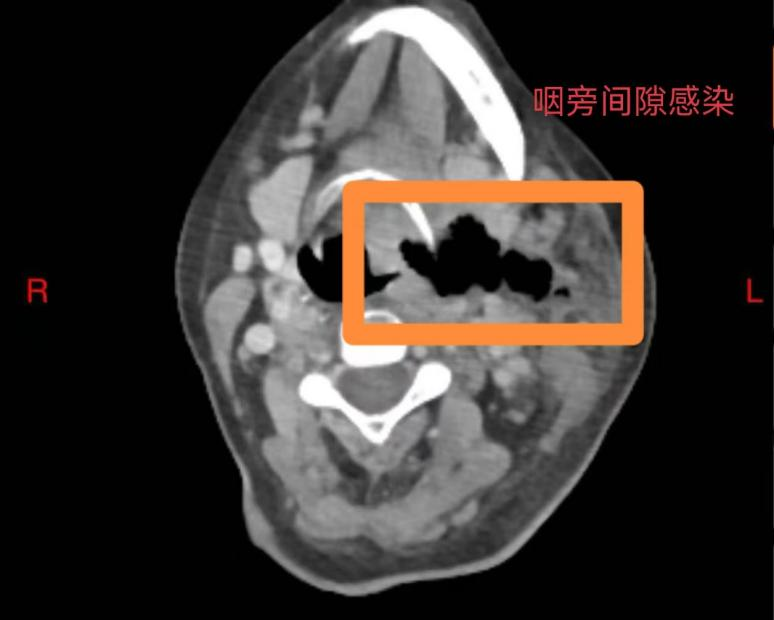

60岁的庄女士未曾想到,一场看似寻常的牙痛,竟会迅速发展为危及生命的重症。庄女士糖尿病多年未经规范治疗,口腔卫生欠佳,口内牙齿时不时疼痛、松动、脱落,患者总认为牙疼是小毛病,吃点甲硝唑就好了,从未重视。5 天前,左下后牙疼痛后患者依旧未经重视,很快就出现咽部、…